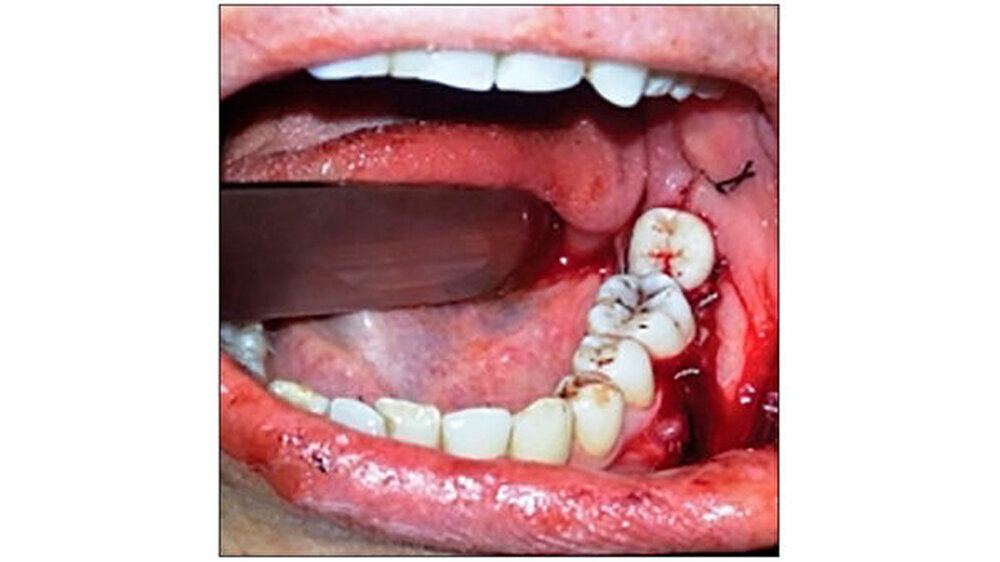

Eine 27-jährige Patientin stellte sich mit Schmerzen im linken Unterkiefer in der Abteilung für Zahnerhaltung und Endodontie am Himachal Dental College in Himachal Pradesh , Indien, vor. Die klinische und radiologische Untersuchung ergab, dass der Zahn 37 stark kariös war. Zudem lag eine chronische irreversible Pulpitis und apikale Parodontitis vor. Der Zahn 38 zeigte horizontale Einbrüche (Abbildung 1). Daher wurde beschlossen, 37 und 38 gleichzeitig zu extrahieren und den 38 in die Extraktionsstelle des 37 zu transplantieren.

Die Anästhesie erfolgte mit Lidocain-Hydrochlorid (Lignox zwei Prozent, Indoco-Remedies Ltd., India). Zuerst erfolgte die Extraktion von Zahn 37 extrahiert - ohne die Corticales zu beschädigen. Danach erst erfolgte die Extraktion von Zahn 38, um hier die Gewebeschäden so gering wie möglich zu halten. Eine horizontale intrakrevikuläre Inzision wurde durchgeführt. Zahn 38 wurde bis zur Transplantation in isotoner Kochsalzlösung gelagert, parallel eine Socket Preparation vorbereitet (Abbildung 2).